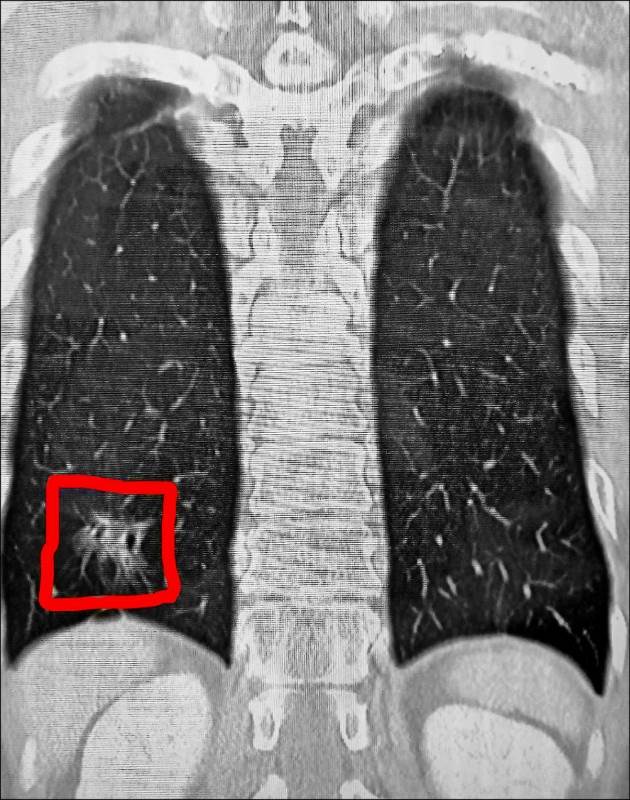

根據《TVBS新聞網》、《自由時報》報導,謝志明主任仔細分析陳先生的斷層掃描影像,赫然發現他的右下肺葉出現疑似癌癥的病灶。

當時陳先生的交通事故傷勢在住院治療2週後就順利出院,但那塊毛玻璃樣的肺部陰影卻讓醫師相當擔憂。由于肺腺癌被稱作「隱形殺手」,早期幾乎沒有任何癥狀,許多患者發現時往往已經來不及了。

3個月後陳先生回診追蹤肋骨復原狀況,謝醫師發現那處病灶依舊存在,立刻安排他接受第2次「胸腔鏡微創手術」將病灶切除。病理化驗結果證實醫師的判斷沒錯,陳先生確實罹患肺腺癌第1期。謝醫師解釋,一般胸部X光很難偵測到1公分以下的微小病變,許多肺癌病患確診時病情已經相當嚴重。